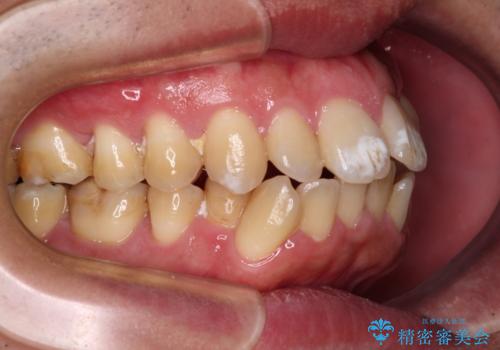

- 前歯の捻れを気にして来院された患者様です。

上顎前歯が捻れて前方に飛び出しており、下顎前歯もそれに沿うようにデコボコとなっていました。

IPR(歯と歯の間を削る処置)によりスペースを獲得して上下前歯のデコボコを改善し、インビザラインにて矯正治療を行うこととしました。

捻れていた前歯の形態が、先端が欠けていたり、一部むし歯処置により左右非対称の形態となっていたため、なかなかゴールが定まらず、治療期間がかかってしまいました。